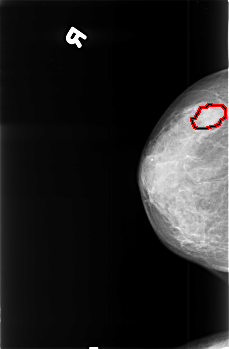

B_3396_1.RIGHT_CC

RIGHT_CC LINES 4528 PIXELS_PER_LINE 2976 BITS_PER_PIXEL 12 RESOLUTION 50 OVERLAY

FILE: B_3396_1.RIGHT_CC.OVERLAY

TOTAL_ABNORMALITIES 1

ABNORMALITY 1

LESION_TYPE MASS SHAPE IRREGULAR MARGINS OBSCURED

ASSESSMENT 4

SUBTLETY 3

PATHOLOGY MALIGNANT

TOTAL_OUTLINES 1

BOUNDARY